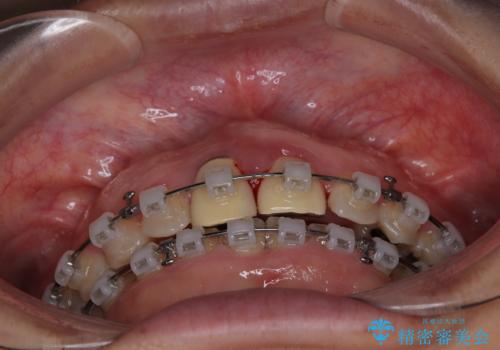

- クリアブラケット

マウスピース装着は煩わしいとのことで、表側のワイヤー装置にて矯正治療を行うこととしました。